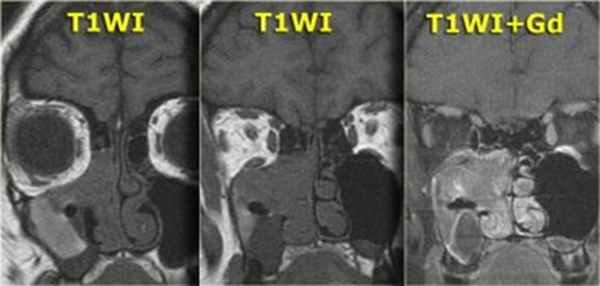

Переходно-клеточная папиллома

редкая, но характерная для полости носа и его синусов доброкачественная опухоль. Чаще встречается у мужчин. Как правило, она возникает на боковой стенке полости носа, а также в околоносовых пазухах. Из полости носа опухоль может врастать в околоносовую пазуху и наоборот. Пациенты обычно жалуются на заложенность носа, выделения, носовые кровотечения, боль в области лицевого нерва. Иногда в зоне опухолевого роста происходит разрушение костной ткани.

Переходно-клеточная папиллома с ремоделированием костных стенок

Образование в центре среднего носового хода, накапливающее контрастное вещество, распространяется в верхнечелюстную пазуху и/или ячейки лабиринта решетчатой кости